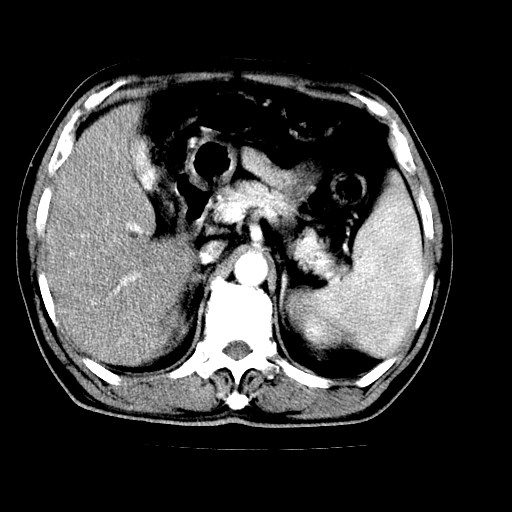

男,66岁,上腹部不适、黄染一周。彩超示:肝左叶占位,肝内胆管扩张,胆总管扩张,胆总管占位?

肝左叶不规则软组织肿块影,边缘不规整邻近肝实质受累分界不清;肝内胆管(左叶)明显扩张成“软藤状”,诊断:肝左叶胆管细胞癌。

肝左叶占位性病变,并胆管扩张,符合胆管细胞癌ct表现,门脉左支受累,左肾囊肿。窗宽太窄了,其他的看不清

支持肝左叶肝内胆管细胞癌伴胆总管及门脉左支受侵。

胆囊缩小,其内胆汁浓缩,也提示梗阻部位应该位于胆囊管起始部以上或是胆囊管受累及,支持肝外胆管癌。